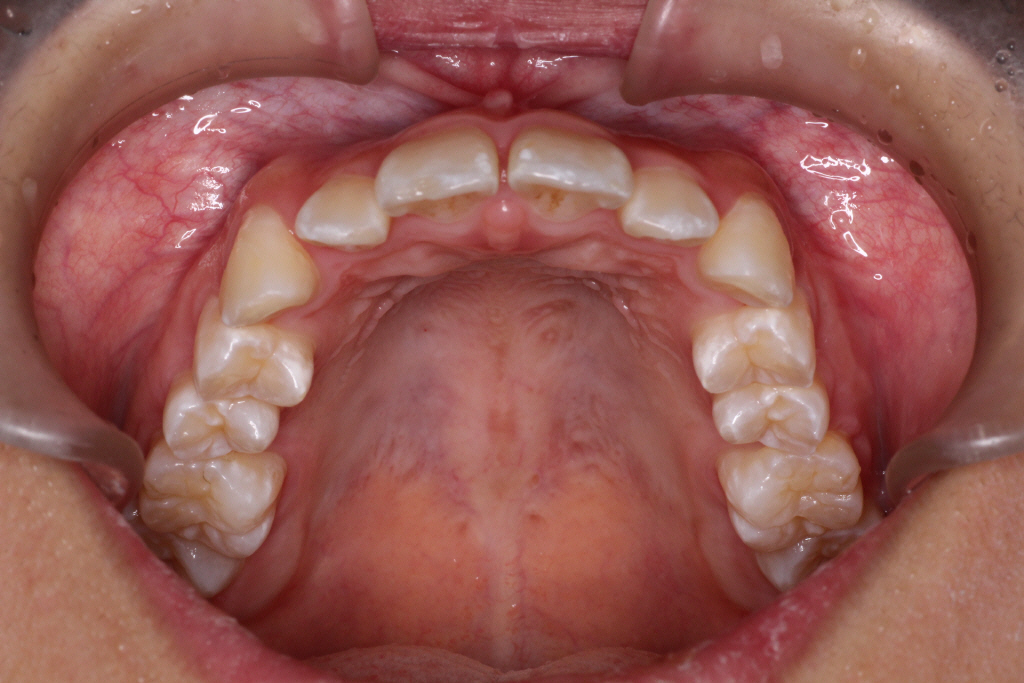

最後のアライナーが終わった時の口腔内写真です。

前歯のがたつきはなくなり、カリエール後にできていた隙間もなくなっています。

奥歯も1歯対2歯の関係で咬めていることがわかります。

通常は歯の並びを微調整するために口腔内を再スキャンし、歯の並びを再設計すること(リファイメント) を2,3回行いますが今回のケースは一回目で満足のいく結果が得られたのでここで保定期間に入りました。